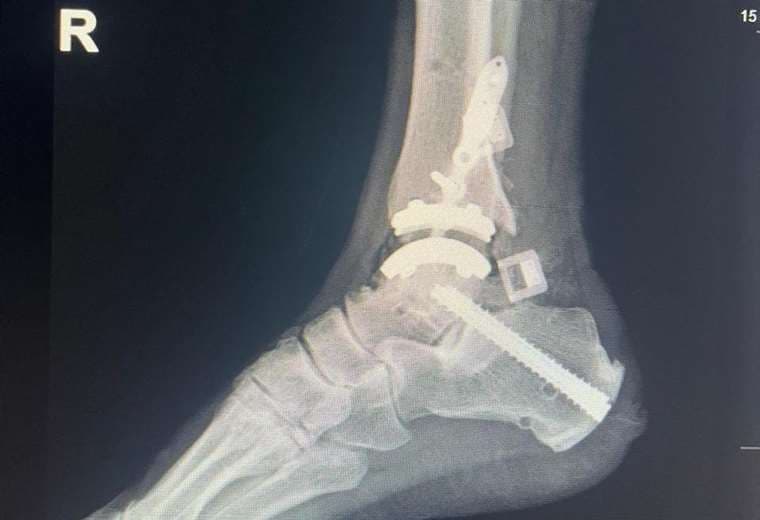

El Centro Nacional de Rehabilitación (Cenare) realizó, por primera vez en su historia, un reemplazo de tobillo con una prótesis artificial a un paciente de 66 años.

La institución administradora de los centros de salud públicos precisó que el adulto mayor recibió la prótesis en el tobillo derecho y que hasta el cierre de esta publicación se recupera satisfactoriamente, tras cinco horas de cirugía.

También se contó con apoyo técnico de la empresa estadounidense que fabrica los implantes, Zimmer-Biomet.